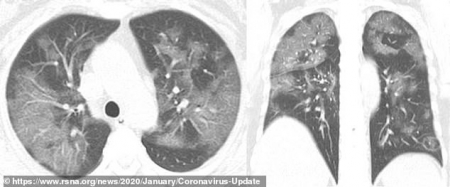

আপনাদের বোঝার সুবিধার্থে আক্রান্ত রোগীর বুক ও সাধারণ রোগীর বুকের দুইটি এক্সরের ছবি নিচে দেওয়া হলোঃ

করোনা আক্রান্ত রোগীর ফুসফুস বা LUNGS।

শাহ আজিজ বলেছেন: সি টি স্ক্যানে আরও পরিচ্ছন্ন ছবি পাওয়া যায় । মার্চ মাসে উহানের রোগীদের স্ক্যান চিত্র হংকঙের একটি পত্রিকা ছাপত । পড়ে পুরো লকডাউন আর ইন্টারনেট বন্ধ হয়ে গেলে আমরা খবর পাওয়া থেকে বঞ্চিত হই । একটি ক্লোজ ছবিতে দেখাচ্ছিল গুরুতর সংক্রমিত এবং বেচে যাওয়া এক রোগীর লাংস । গ্লাস গলে গেলে যেমন দুমড়ে মুচড়ে যায় সেই রোগীর তাই হয়েছে । হংকঙ্গের ডাক্তার বলছিলেন এই ধরনের বেচে যাওয়া রোগী বাকি জীবন লাংসের বিবিধ ওষুধ খেয়ে বেচে থাকবেন । আমি খুজব সেই ক্লিপ সেভ করেছিলাম কিনা । এক্সরে নয় সিটি স্ক্যান বেশি উপযোগী , খরচ বেশি বলে তা করা হয় না ।

রোকনুজ্জামান খান বলেছেন: আপনার কথার গ্রহনযোগ্যতা আছে এবং আমি আপনার সাথে একমত। সিটি স্ক্যান অফ চেষ্ট করালে আরো সুন্দর ও পরিচ্ছন্ন ভাবে আমরা দেখতে পারি। তবে আমাদের দেশের ডাক্তাররা কভিড পরীক্ষার কাছেই দায়বদ্ধ। এখনো অনেক জেলা শহর গুলোতে সিটি স্ক্যান অফ ব্রেন ছাড়া অন্য কোন সিটি করানো হয় না। এক্সরে আমাদের জন্য সহজলভ্য ও অল্পমূল্যের তাই এটিকে প্রাধান্য দেওয়া হয়েছে। আপনার কার্যকরী মন্তব্যের জন্য সাধুবাদ ও অন্তরিক ধন্যবাদ জানাচ্ছি। এবং সুস্বাস্থ্যে কাটান প্রতিটি সময়, আপানি এবং আপনার পরিবার সেই কামনা রইলো।

Covid-19 stage 10-13days।